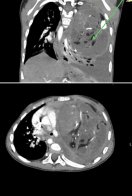

Львівські медики врятували життя маленькій львів’янці, у якої виявили велику пухлину середостіння, що здавлювала легеню та зміщувала життєво важливі органи. Стан дитини ускладнювала важка інфекція. Про це повідомили у Центрі дитячої медицини 9 січня.

“У дитини виявили велике пухлинне утворення в лівій половині грудної клітки, яке повністю здавлювало ліву легеню та зміщувало життєво важливі органи. Ситуацію ускладнювала генералізована інфекція: стандартна агресивна хіміотерапія могла бути надзвичайно небезпечною. Проте через масивні розміри пухлини й компресію легені чекати було неможливо”, — розповіла онкологиня Неля Вовк.

Пухлину вдалося повністю видалити та усунути здавлення органів і відновити їх нормальне положення. Після операції маленька Аня продовжила хіміотерапію, щоб мінімізувати ризик рецидиву. Врешті контрольні обстеження, зокрема ПЕТ-КТ у грудні, показали, що ознак активного онкологічного процесу не виявлено.